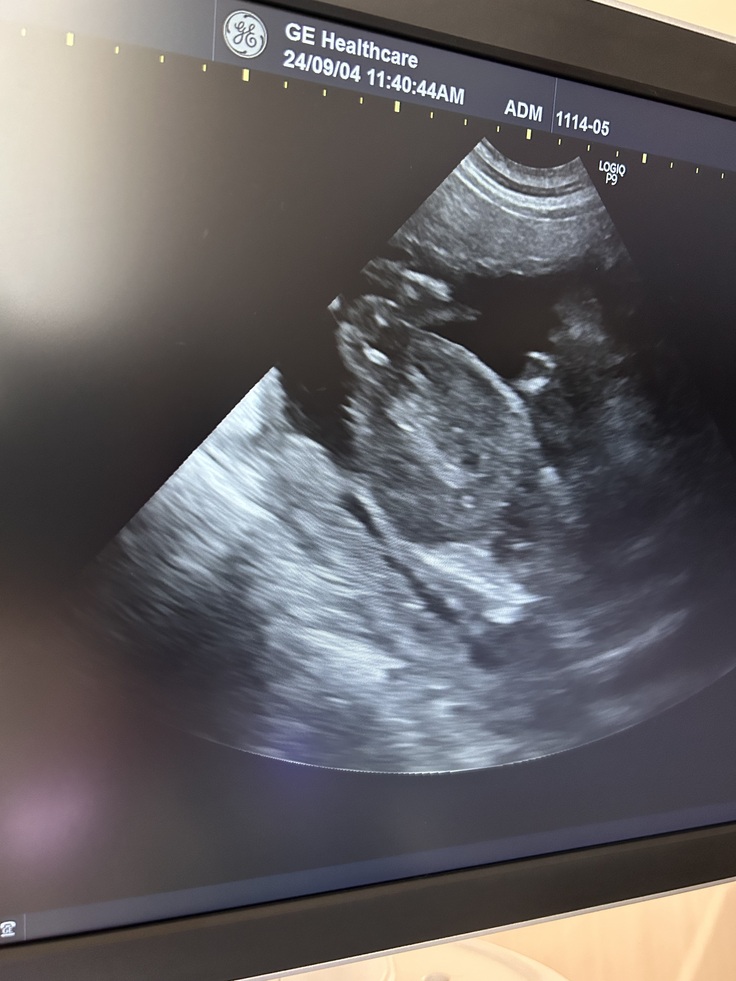

そこで、数日前にかかりつけの動物病院に超音波診断に行きました。

今回、超音波診断をしてくださった先生は、ちょうど一年前、レラが人工交配後にも検査してくれた同じ先生でした。

診断が始まりました。

昨年、二人でレラの交配失敗を画面越しに見届けたときと同じような重たい空気を一瞬感じましたが。。。先生は私を動揺させないようにか、とても明るい表情で、レラのお腹に触手をあてながら「レラちゃん、いるかな、いるかな。。。」と検査を進めてくださいます。

そして、しばらく探した後、「いたよ!!ちゃんと元気に心臓も動いていますよ。レラちゃん、良かったね~!!!」

私もアラスカの病院では診察室に入れなかったので、レラの胎児のエコー動画を見るのは初めて。「レラ、良かったな、良く頑張ったな。」と、自然と声を出ました。